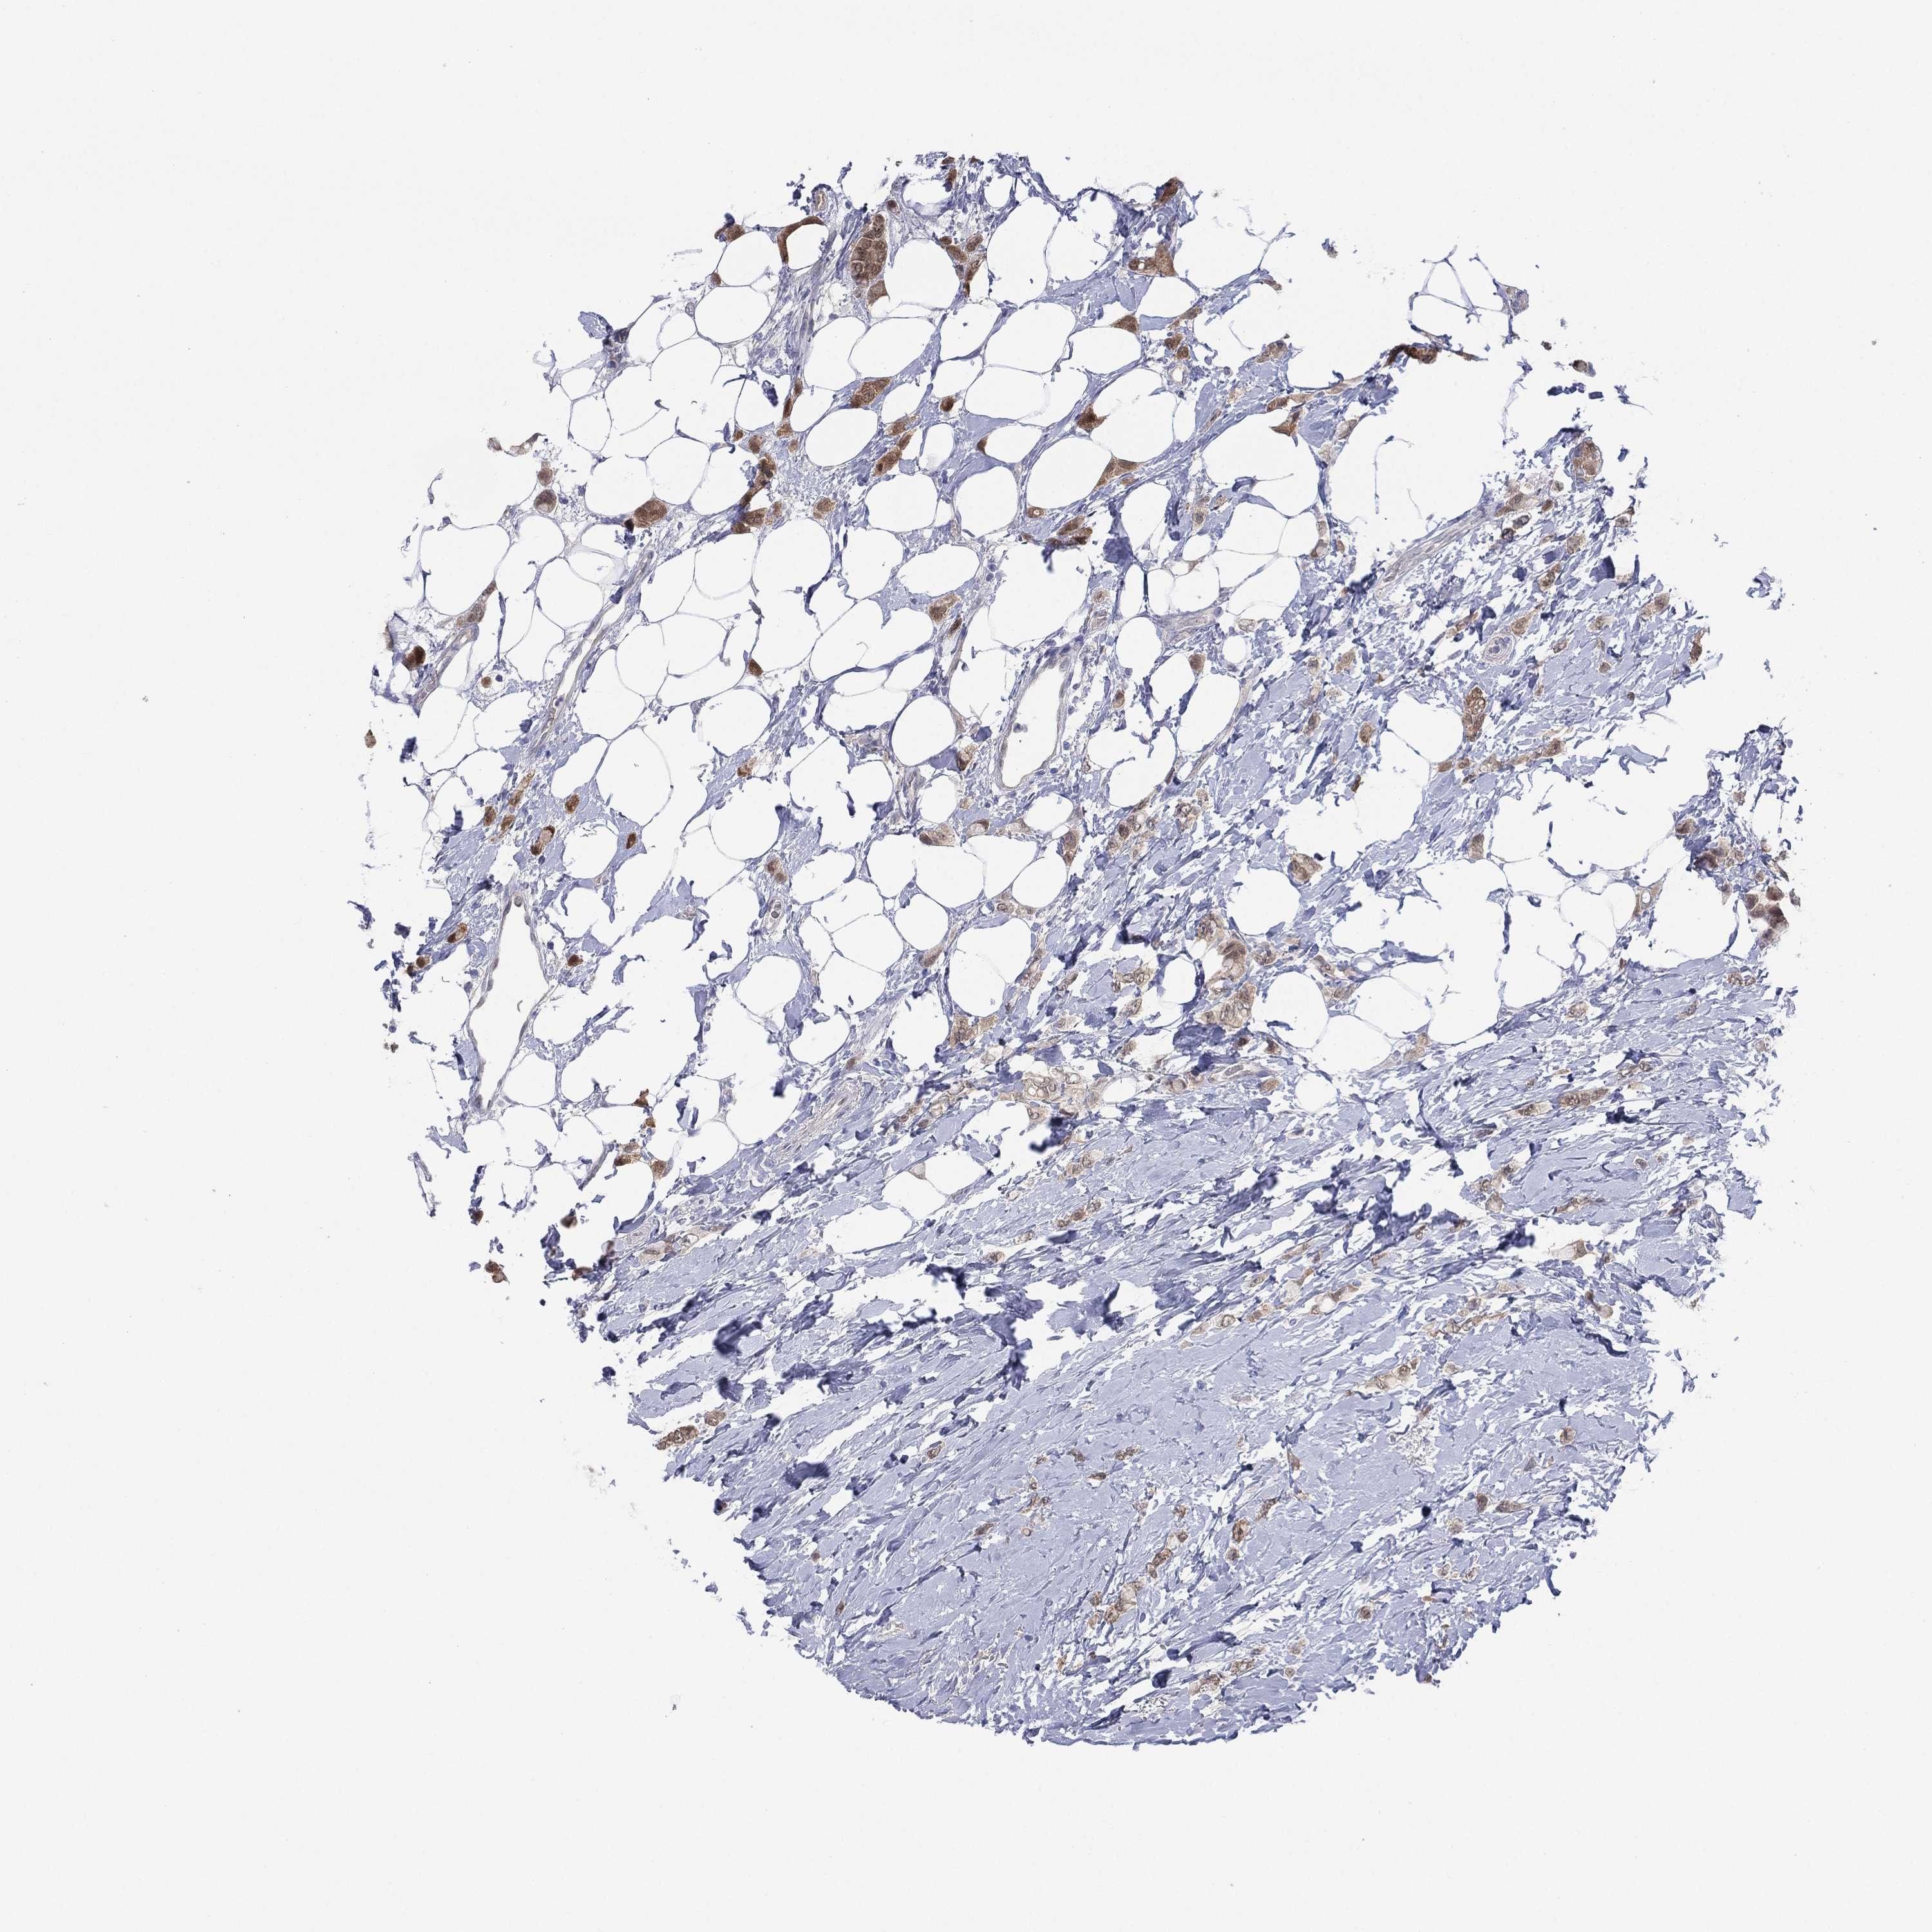

CANCER BREAST CANCER Show tissue menu

BRCA TCGA BRCA VALIDATION PROTEIN EXPRESSION

ANTIBODIES

AND

VALIDATION